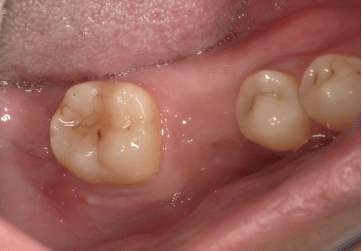

2025.11.0930代男性「他院で抜歯後、ブリッジ・部分入れ歯・インプラントで悩んでいる」欠損部を切開しないインプラント治療をした症例